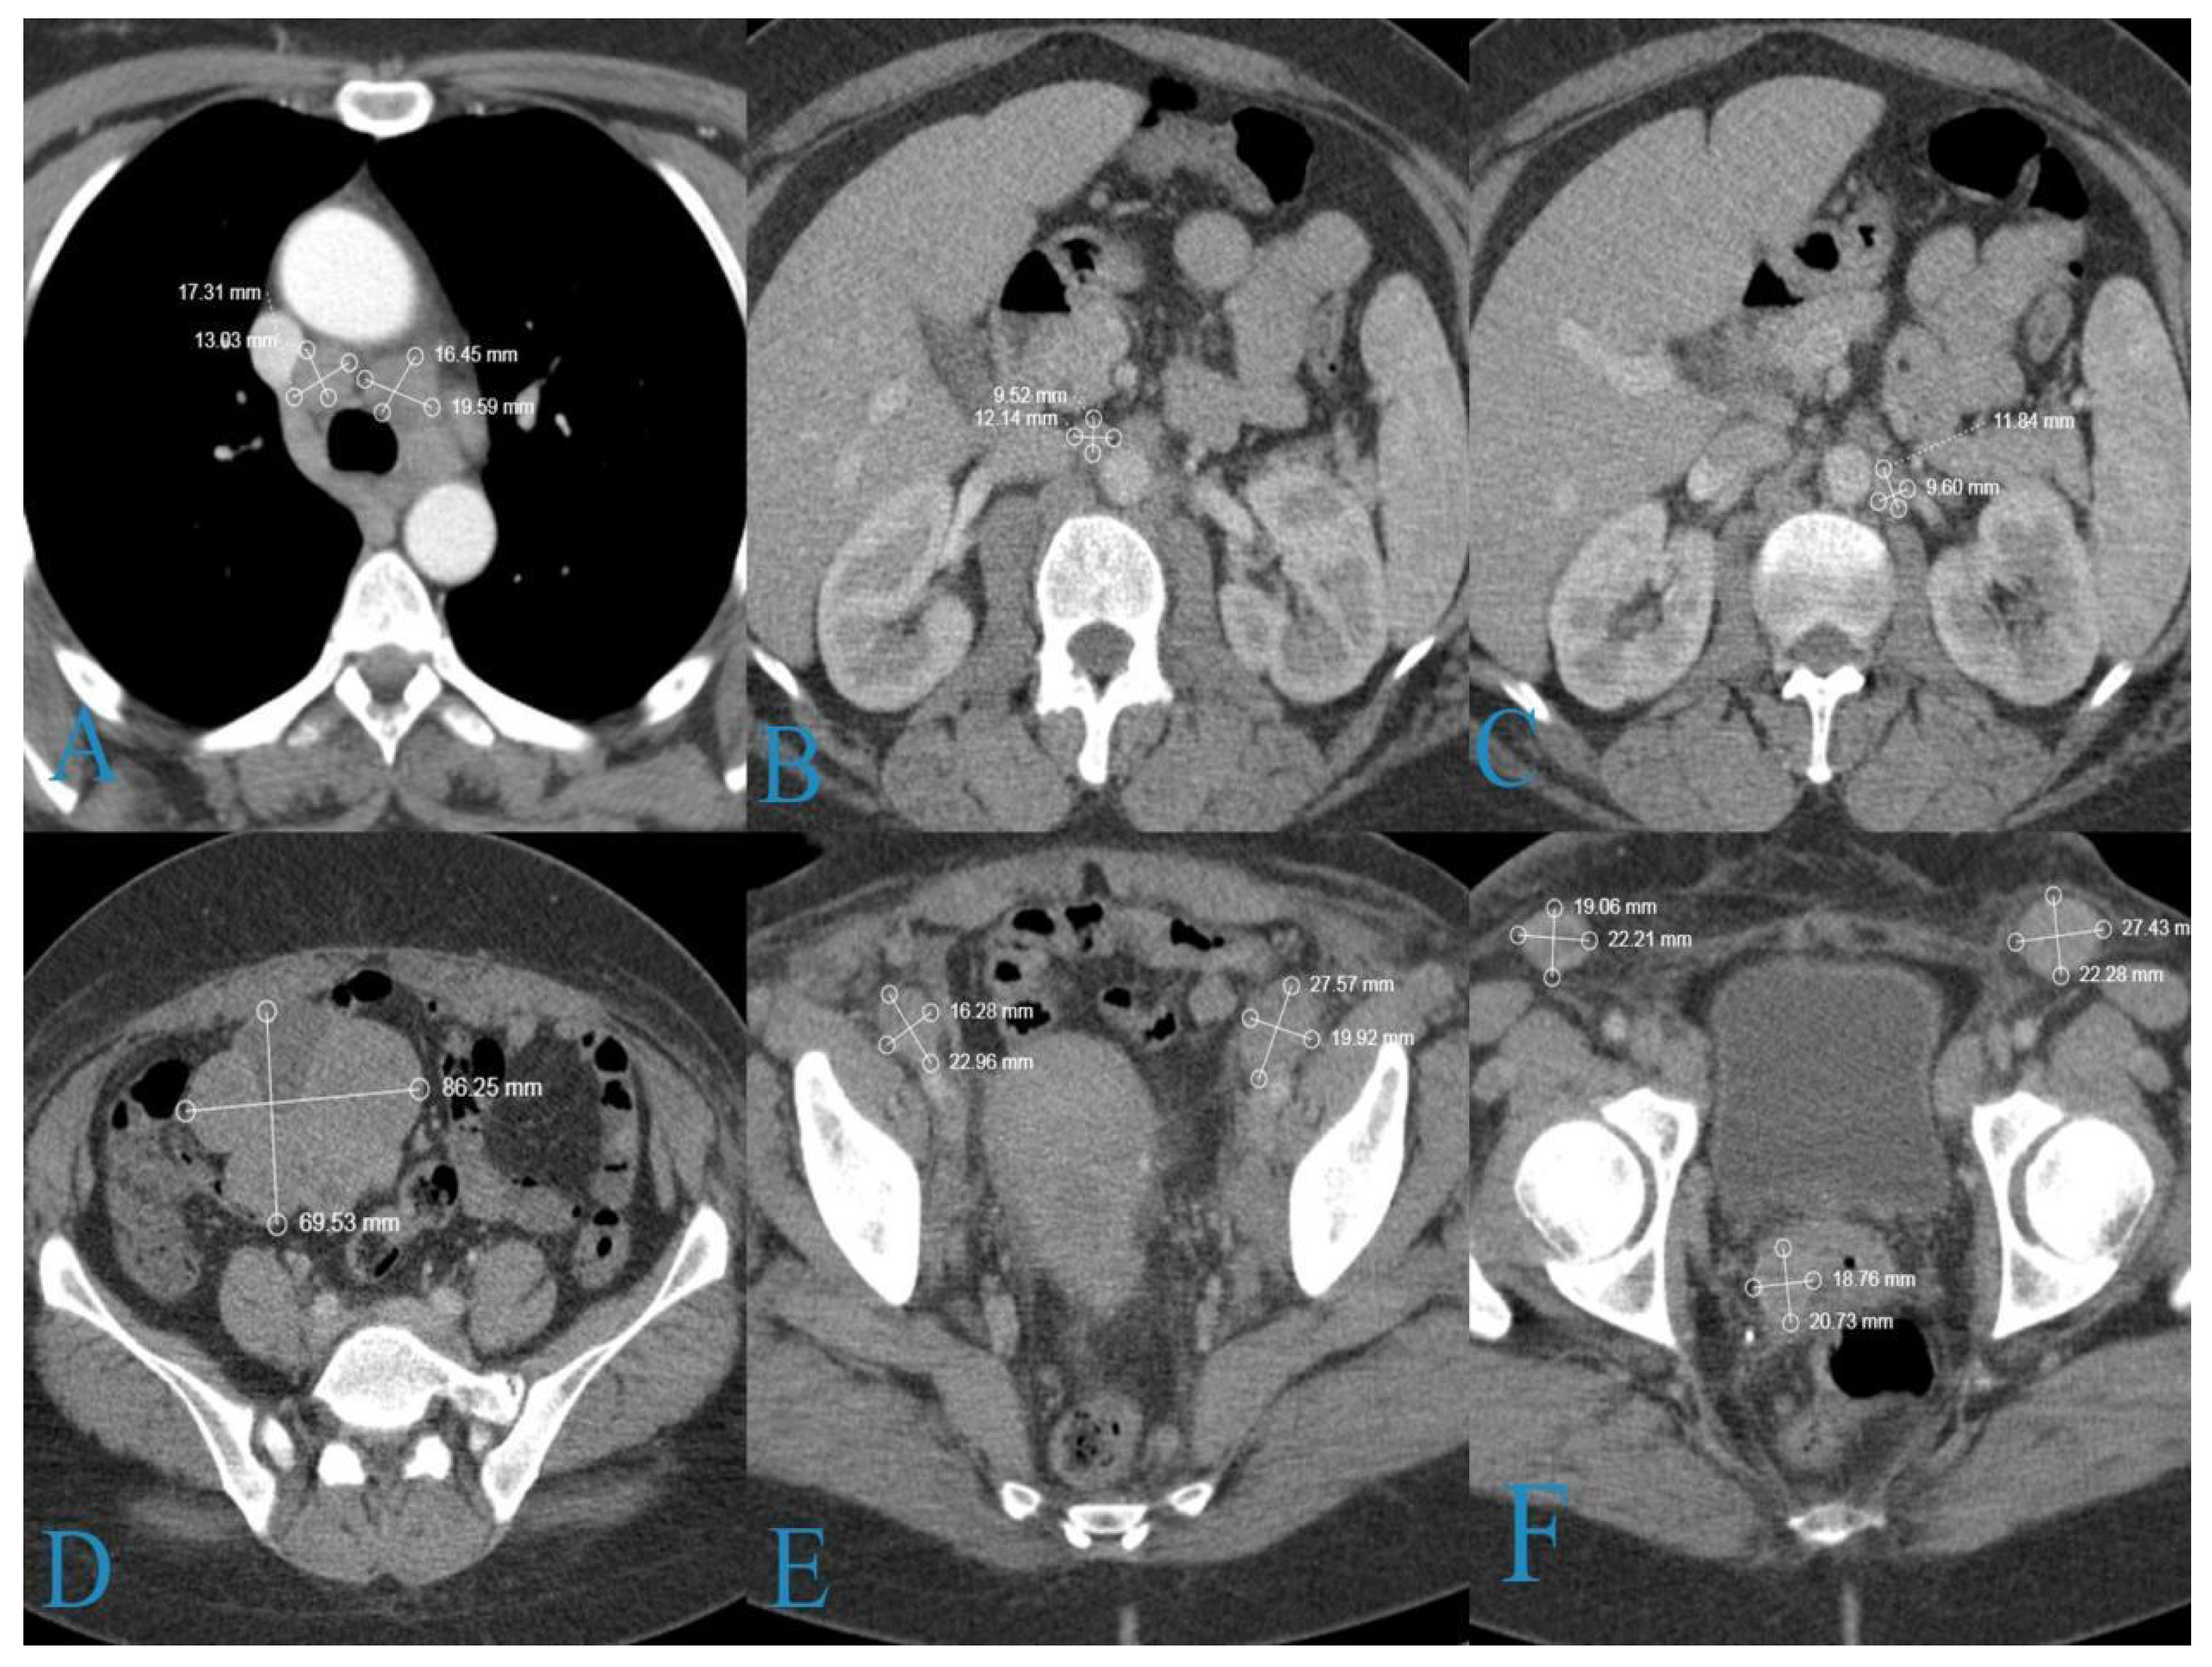

2. Case Report